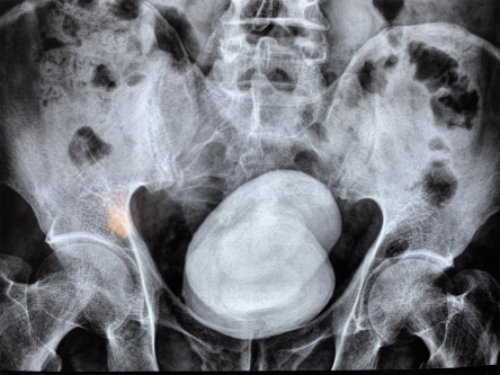

經(jīng)查,鄭先生的膀胱被兩顆直徑長(zhǎng)達(dá)七八公分的結(jié)石充滿,從X光片上看,這對(duì)超大號(hào)結(jié)石就像一對(duì)“雙胞胎”,霸占著他的膀胱。因結(jié)石巨大,醫(yī)生只能采用膀胱切開取石的方法將石頭取出。當(dāng)醫(yī)生把兩個(gè)拳頭大的結(jié)石拿給他看時(shí),他對(duì)自己久拖不治的行為懊悔不已。